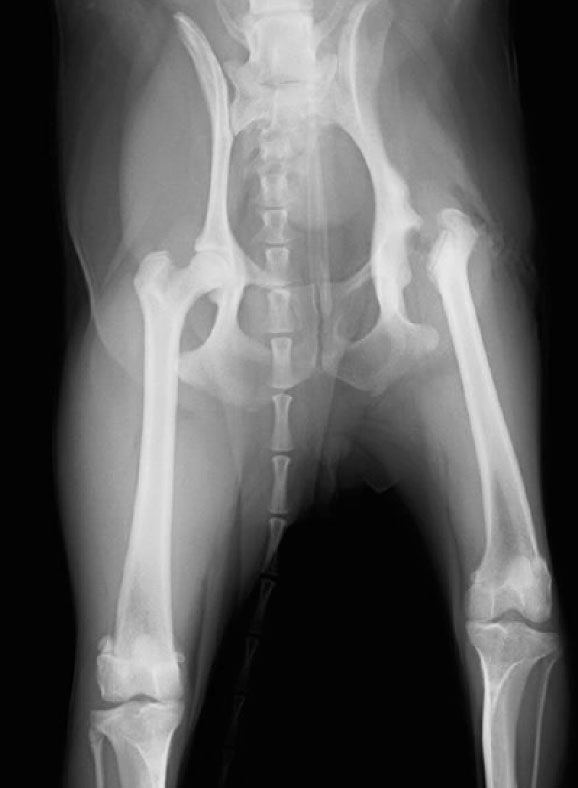

大腿骨頭切除(FHO)術後